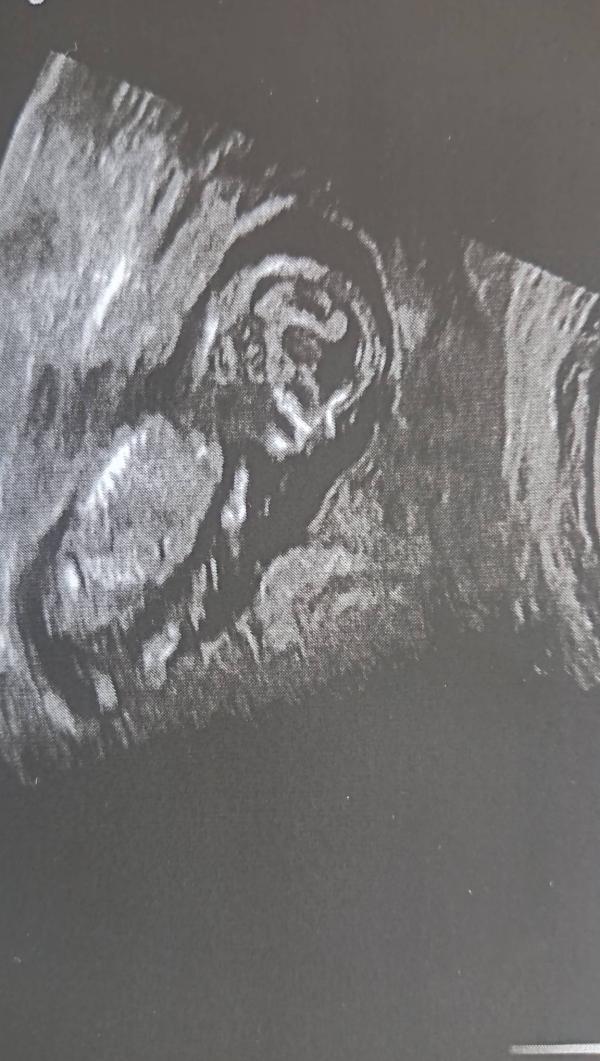

Скрининг 9.04.2024: пол ребенка не увидели, но сказали девочка?

А вот я пошла на платный скрининг 9.04.2024! Пол малыша тоже не увидели, но предположили, что девочка, но не точно)

Да вот как раз таки особо и не увидели только предположение! Старший сын ждёт сестрёнку с нетерпением